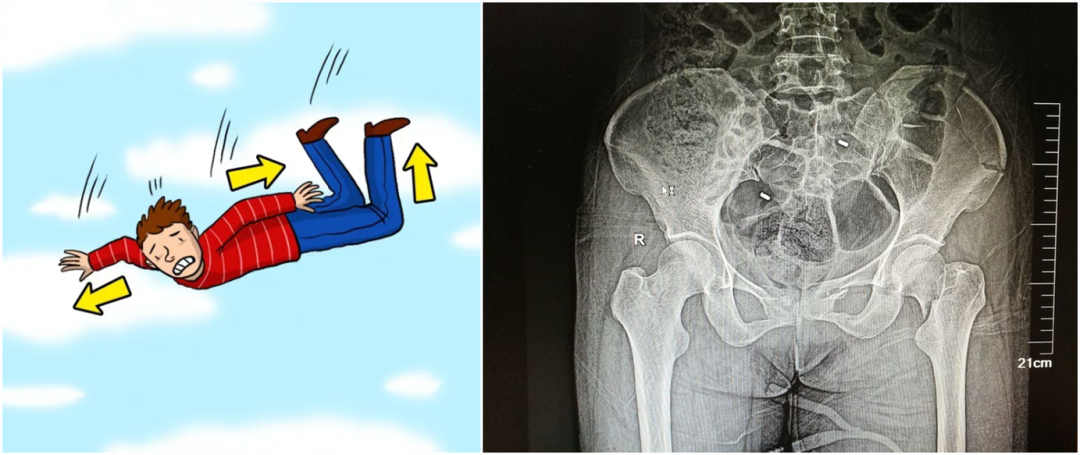

【医疗科普】:外伤性骨折影像

外伤性骨折

从暴力的大小来看,还可以细分为高能量的损伤和低能量的损伤。比如说,如果是车子撞的,从高处坠落,通?;嵩斐筛吣芰康乃鹕?,而普通的跌倒造成的骨折,一般不太严重,可以说是低能量的损伤。